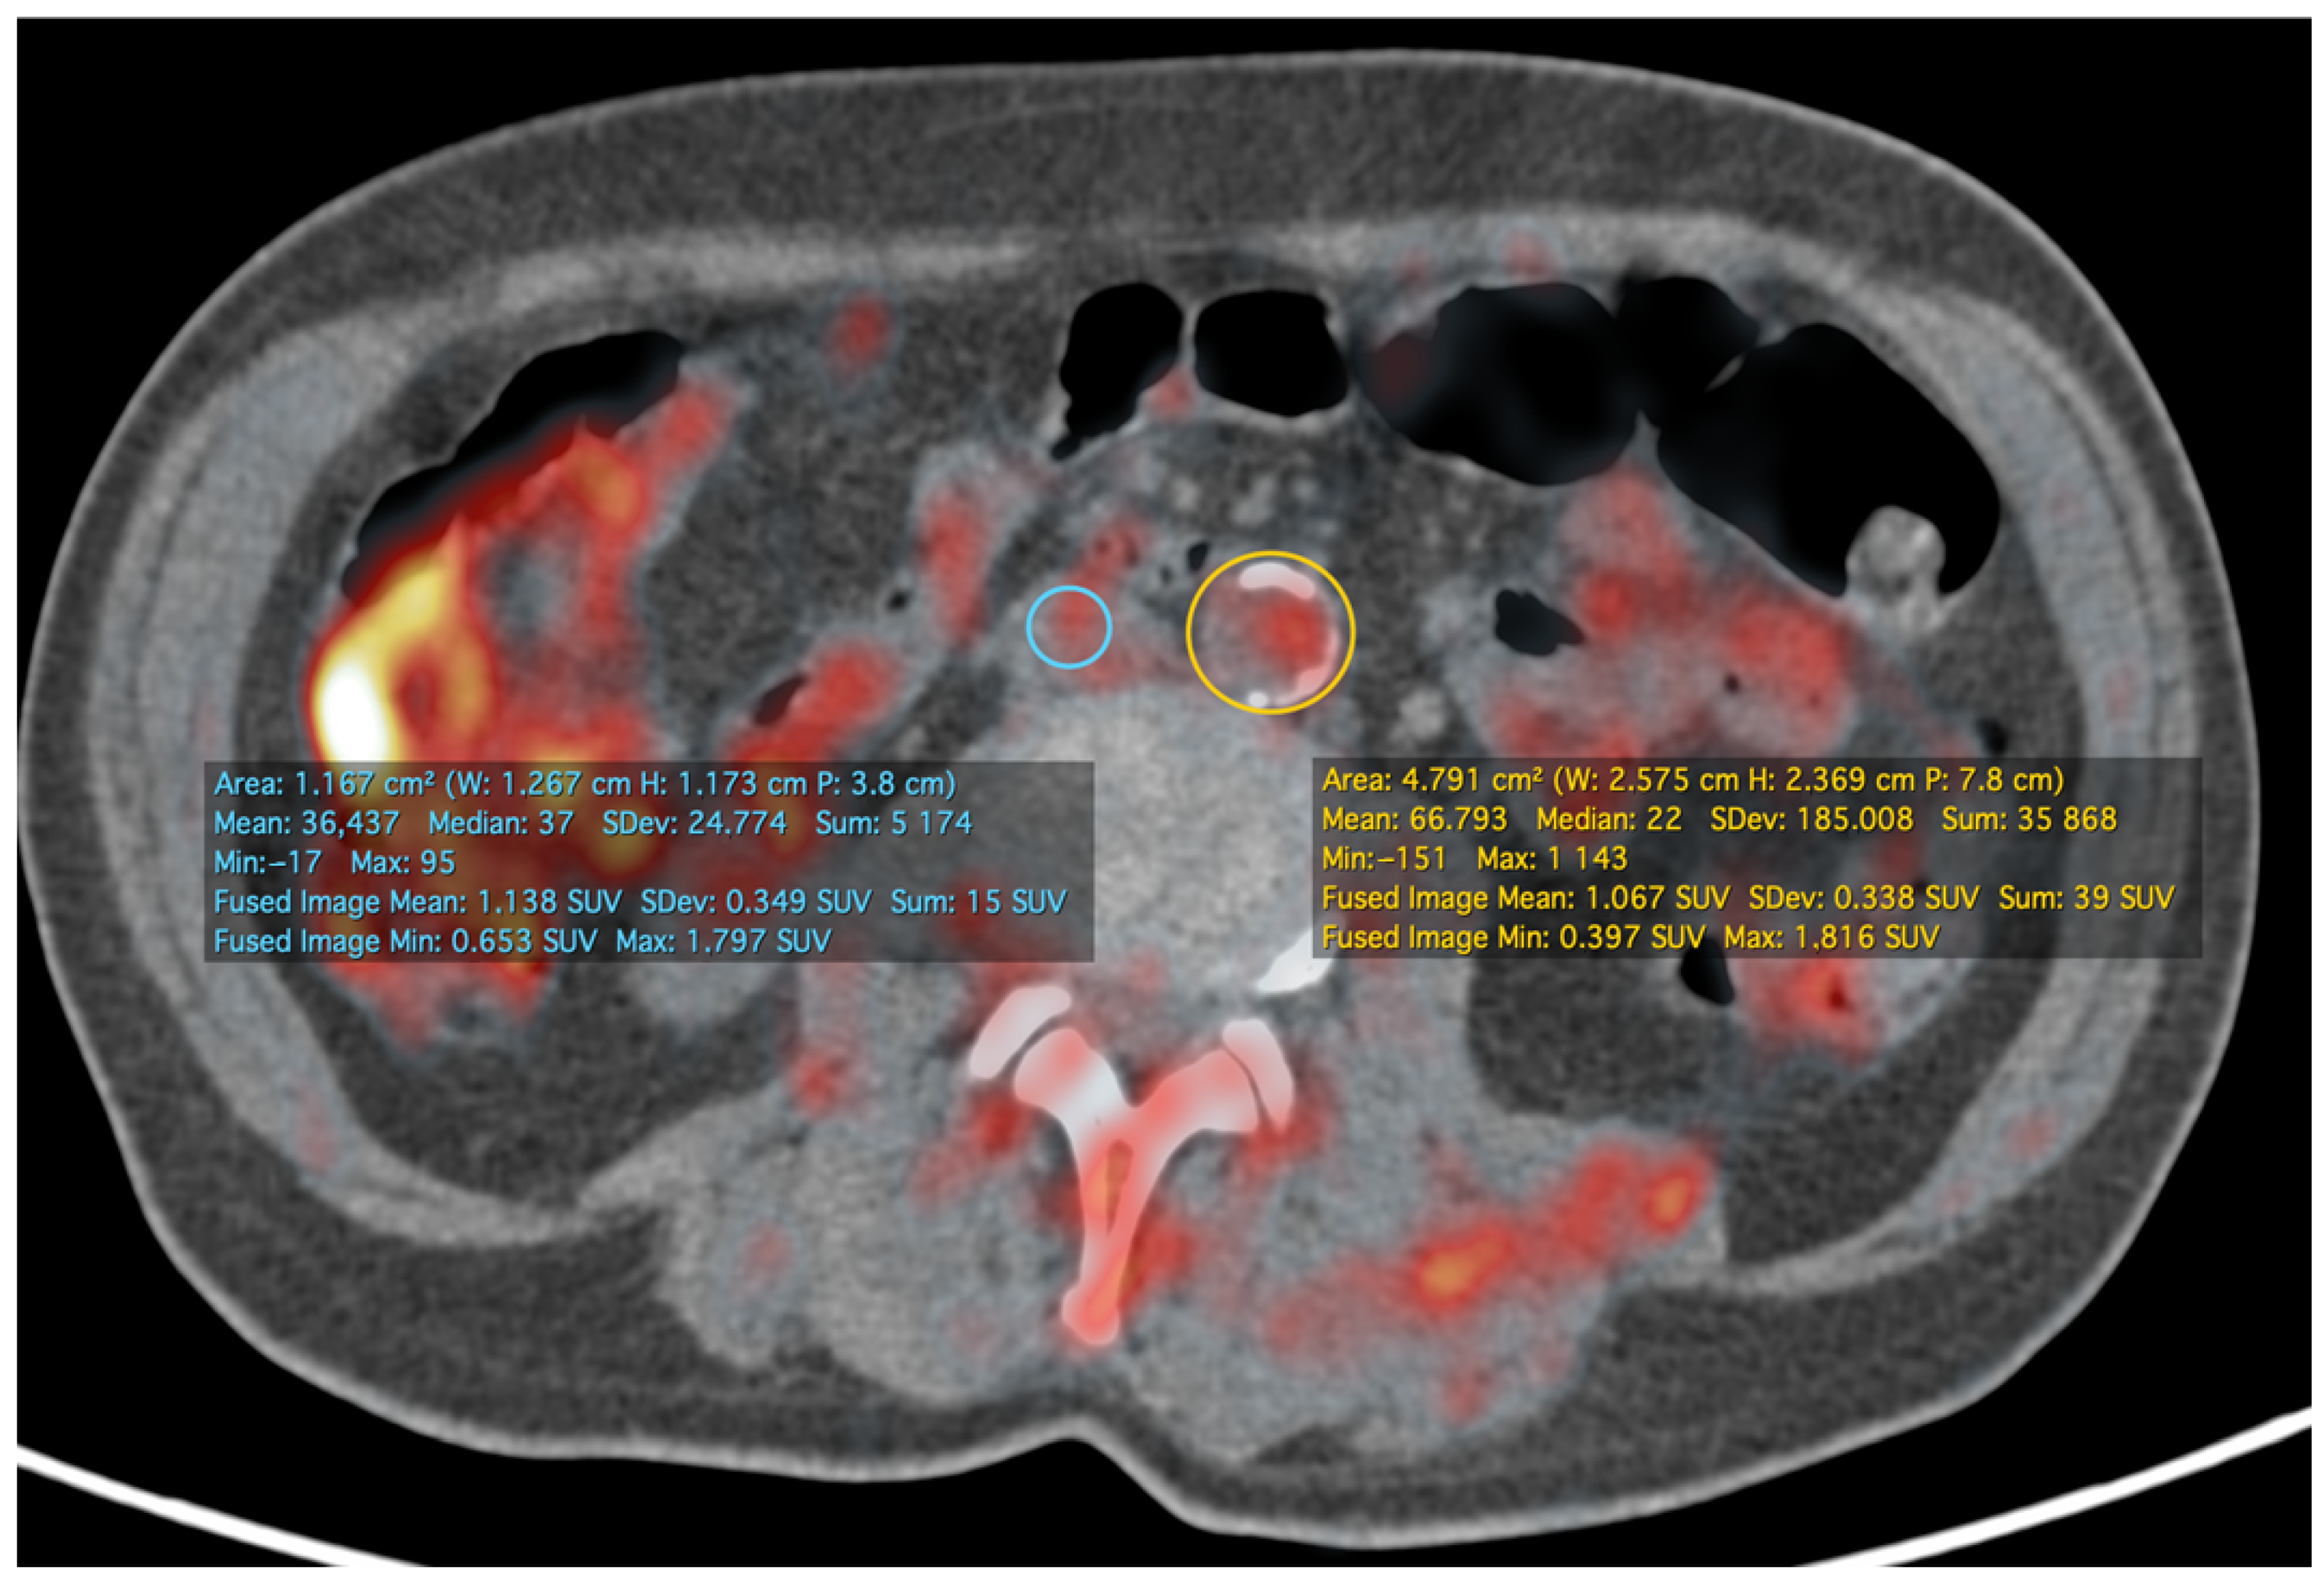

- Koa, B.; Borja, A.J.; Yellanki, D.; Rojulpote, C.; Tran, J.; Zhang, V.; Werner, T.J.; Alavi, A.; Revheim, M.-E. 18F-FDG-PET/CT in the assessment of atherosclerosis in lung cancer. Am. J. Nucl. Med. Mol. Imaging 2021, 11, 1–9. [Google Scholar]

- Rominger, A.; Saam, T.; Wolpers, S.; Cyran, C.C.; Schmidt, M.; Foerster, S.; Nikolaou, K.; Reiser, M.F.; Bartenstein, P.; Hacker, M. 18F-FDG PET/CT Identifies Patients at Risk for Future Vascular Events in an Otherwise Asymptomatic Cohort with Neoplastic Disease. J. Nucl. Med. 2009, 50, 1611–1620. [Google Scholar] [CrossRef] [PubMed]

- Mehta, N.N.; Torigian, E.A.; Gelfand, J.M.; Saboury, B.; Alavi, A. Quantification of Atherosclerotic Plaque Activity and Vascular Inflammation using [18-F] Fluorodeoxyglucose Positron Emission Tomography/Computed Tomography (FDG-PET/CT). J. Vis. Exp. 2012, e3777. [Google Scholar] [CrossRef] [PubMed]